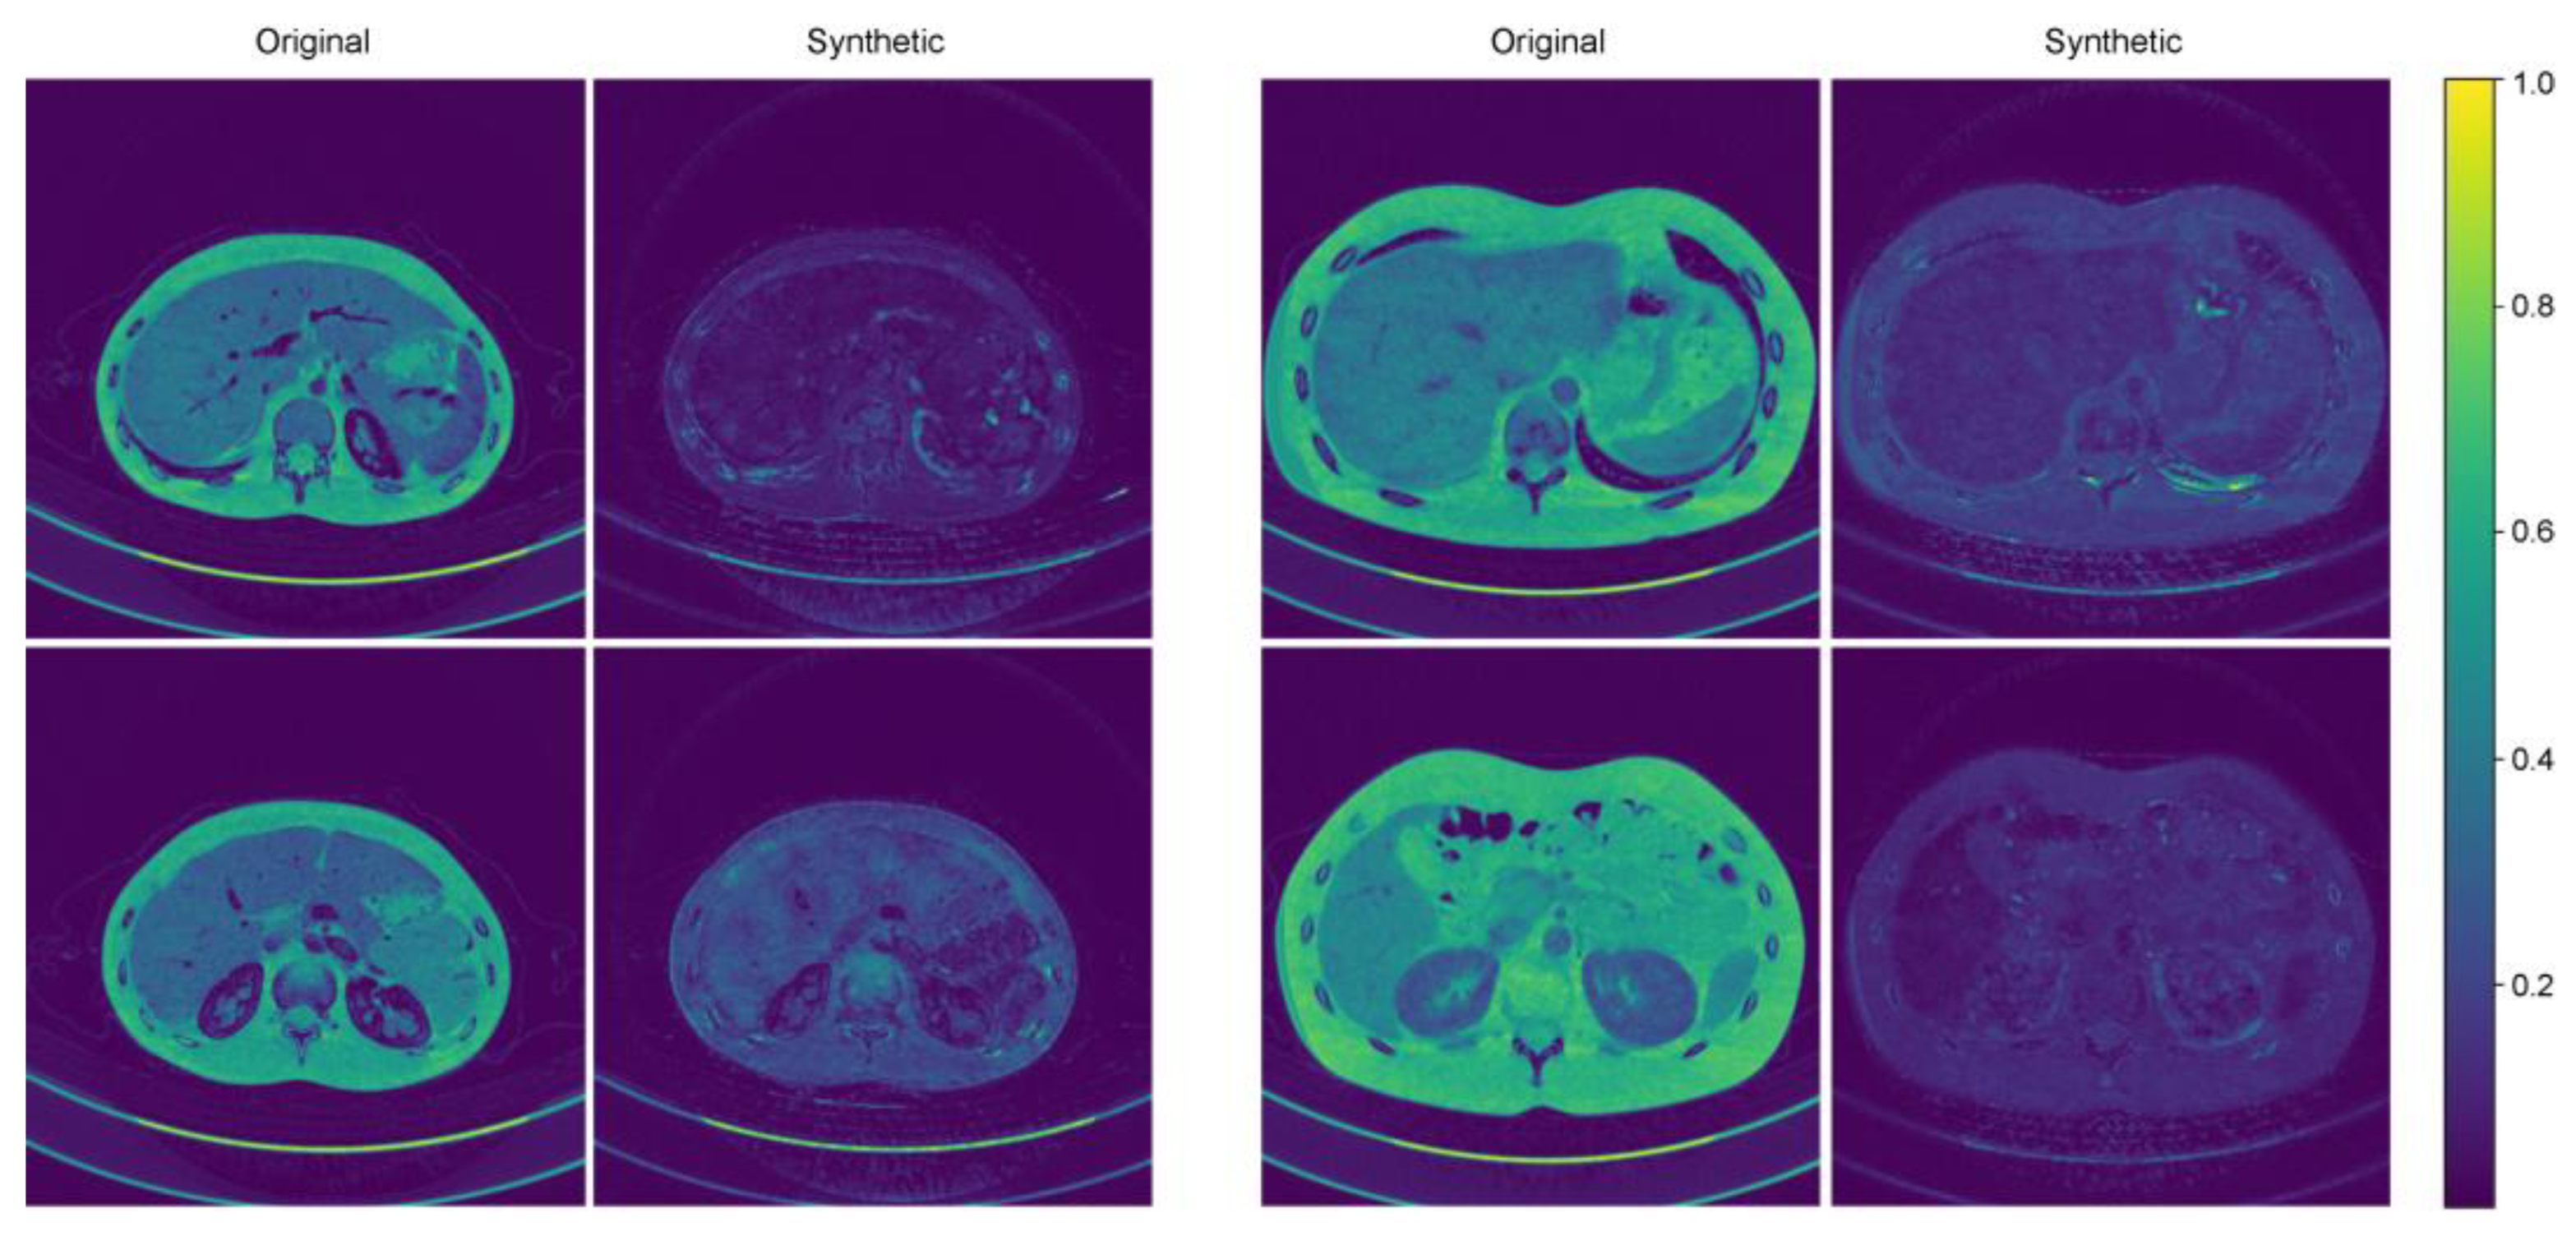

3.3. Standard Deviation Map